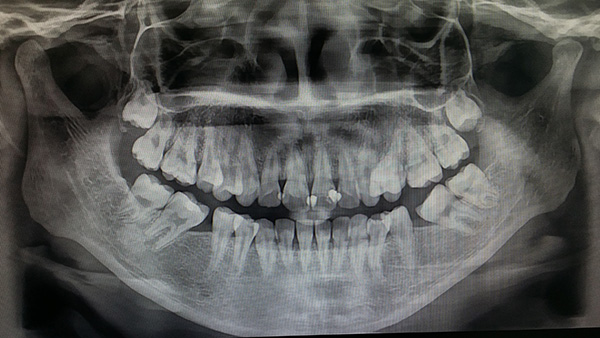

사랑니는 불편함이 없다면 적절한 관리를 받으면서 발치를 하지 않고 지내도 되지만, 정상적으로 나오지 않은 사랑니나 매복 사랑니는 잇몸에 염증을 유발하고 턱뼈 안에 낭종을 유발할 수 있으므로 발치를 해야 합니다. 하지만 사랑니 발치 후 식사 문제로 고민하시는 분들에게 오늘은 정확한 정보를 알려드리겠습니다.